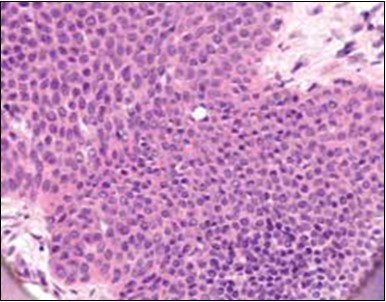

Granular arrangement of malignant cells and intercellular bridges are conspicuous with the demonstration of nuclear atypia, pleomorphism, prominent mitosis and tumour necrosis. A peripheral palisade is discernible within the cellular aggregates. Mitotic figures are common and can be quantified as up to 12 mitosis/ high power field. Tumour differentiation can prominently be of the ductal category with the demonstration of intra-cytoplasmic lumina. Comedo type tumour necrosis is evident along with foci of squamous differentiation The neoplasm is reactive to periodic acid Schiff ‘s (PAS) stain. (Figure 1, Figure 2, Figure 3, Figure 4, Figure 5, Figure 6, Figure 7, Figure 8, Figure 9, Figure 10, Figure 11, Figure 12, Figure 13.

Figure 1.Solid aggregates of tumour cells and duct structures in eccrine porocarcinoma (14).

Classically, intra-epidermal and dermal nests of tumour cells exhibiting cellular atypia and enhanced mitotic activity are enunciated. Tumour aggregates articulate well demarcated, enlarged, atypical polygonal cells with indistinct cellular and nuclear outline, nuclear hyperchromasia , irregular nuclei, vesicular or prominent nucleoli and minimal eosinophilic cytoplasm. Polygonal tumour cells can depict central keratinisation 6, 7.

The neoplasm is composed of lobules of aberrant epithelial cells configured in cords with incrimination of the dermis and epidermis.. Malignant cells congregate within the epidermis or infiltrate the dermis, especially in the primary tumour. Tumour cells within tumour aggregates display a well demarcated cellular outline and appear distinct from encompassing squamous cells. Numerous tumour cell clusters demonstrate a cystic lumen. Prominent epidermal acanthosis is discerned on account of tumour cell proliferation 6, 7.